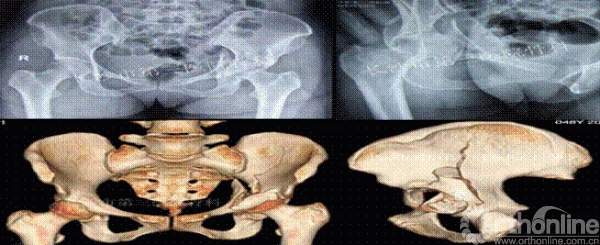

病史资料:患者女性,48岁,因外伤致左髋疼痛活动受限6日入院。6天前因高处坠落致左髋疼痛活动受限,由120急送入院。查生命体征平稳,左髋部略肿胀,左腹股沟广泛压痛,大转子处叩击痛,左下肢纵向叩击痛,左髋主动被动活动受限,左下肢末梢血运、感觉可,无神经功能受损表现。实验室检查(血常规、肝肾功能、血糖、凝血常规、输血前四项、血沉、C反应蛋白)正常,心电图正常。

术前影像

诊断:左髋臼粉碎性骨折。